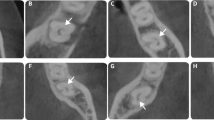

Among the 3315 teeth investigated, 71 (2.14%) presented radix molaris (45 first molars [63.38%] and 26 s molars [36.61%]) (Fig. 1) (P < 0.05) (Table 2). 3244 teeth (97.86%) presented no radix molaris morphology. The prevalence of radix molaris was significantly higher in the first molars (2.92%) compared with the second molars 1.47% (P < 0.05) (Table 2).

CBCT axial slices showing a radix paramolaris (RP) in a second mandibular molar (white arrows).

Bilateral radix molaris were only observed in the first molars (P < 0.05) of 12 CBCT exams who presented this characteristic (20.34%) (Fig. 2) (Table 2).

CBCT axial slice showing the bilateral occurrence of radix entomolaris in mandibular first molars (white arrows).